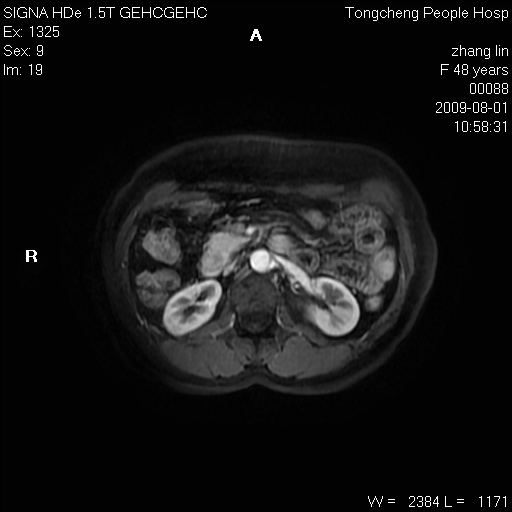

女,48岁。健康体检,彩超发现右肾占位性病变。平素健康。

临床诊断:右肾占位性病变,性质待定(囊肿?肿瘤?)。

上中腹部mr平扫+增强扫描,图像如下:

右肾上极见一类圆形病灶,t1wi呈等信号t2wi呈等高混杂信号,三期增强无强化,边界清---考虑囊肿出血。

同反相位均表现为等信号,病变无强化,考虑含蛋白的囊肿可能,弥散加权相或许有些帮助,